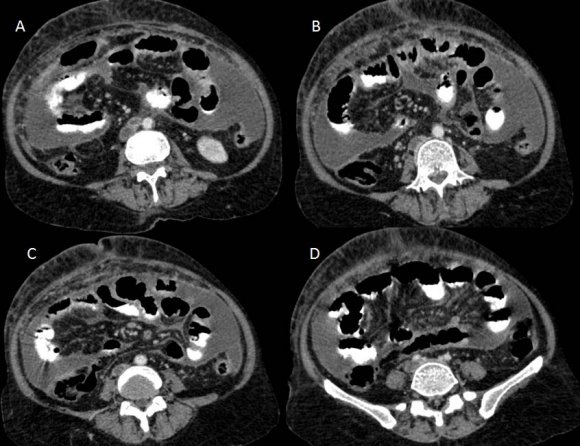

Figure 5. Figure 5 :

5Figure 5: Contrast-enhanced CT scan of the abdomen showing lymph nodes at left para-aortic and inter-aortocaval region (A, B), a filling defect in IVC suggestive of IVC thrombosis (C, D).

Figure 6. Figure 6 :

6Figure 6: Contrast-enhanced CT scan of the abdomen showing lymph nodes in precaval region (A) with thrombosis in IVC (A-C) extending right common iliac vein (D)